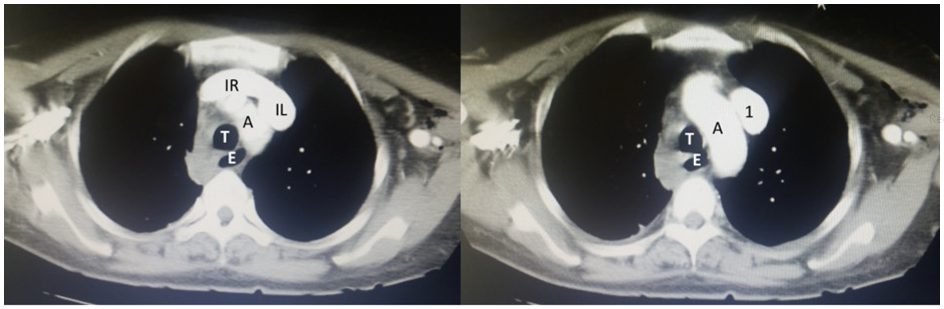

Figure 3 3D Volume rendering reconstruction. 1: LSVC with a vertical pathway through the left side of the mediastinum towards the heart. Note the origin of the LSVC by the junction of both innominate veins (RI and LI respectively).

AA: Aortic Arch; 2: Left Subclavian Vein; 3: Left Jugular Vein; 4: Right Subclavian Vein; 5: Right Jugular Vein